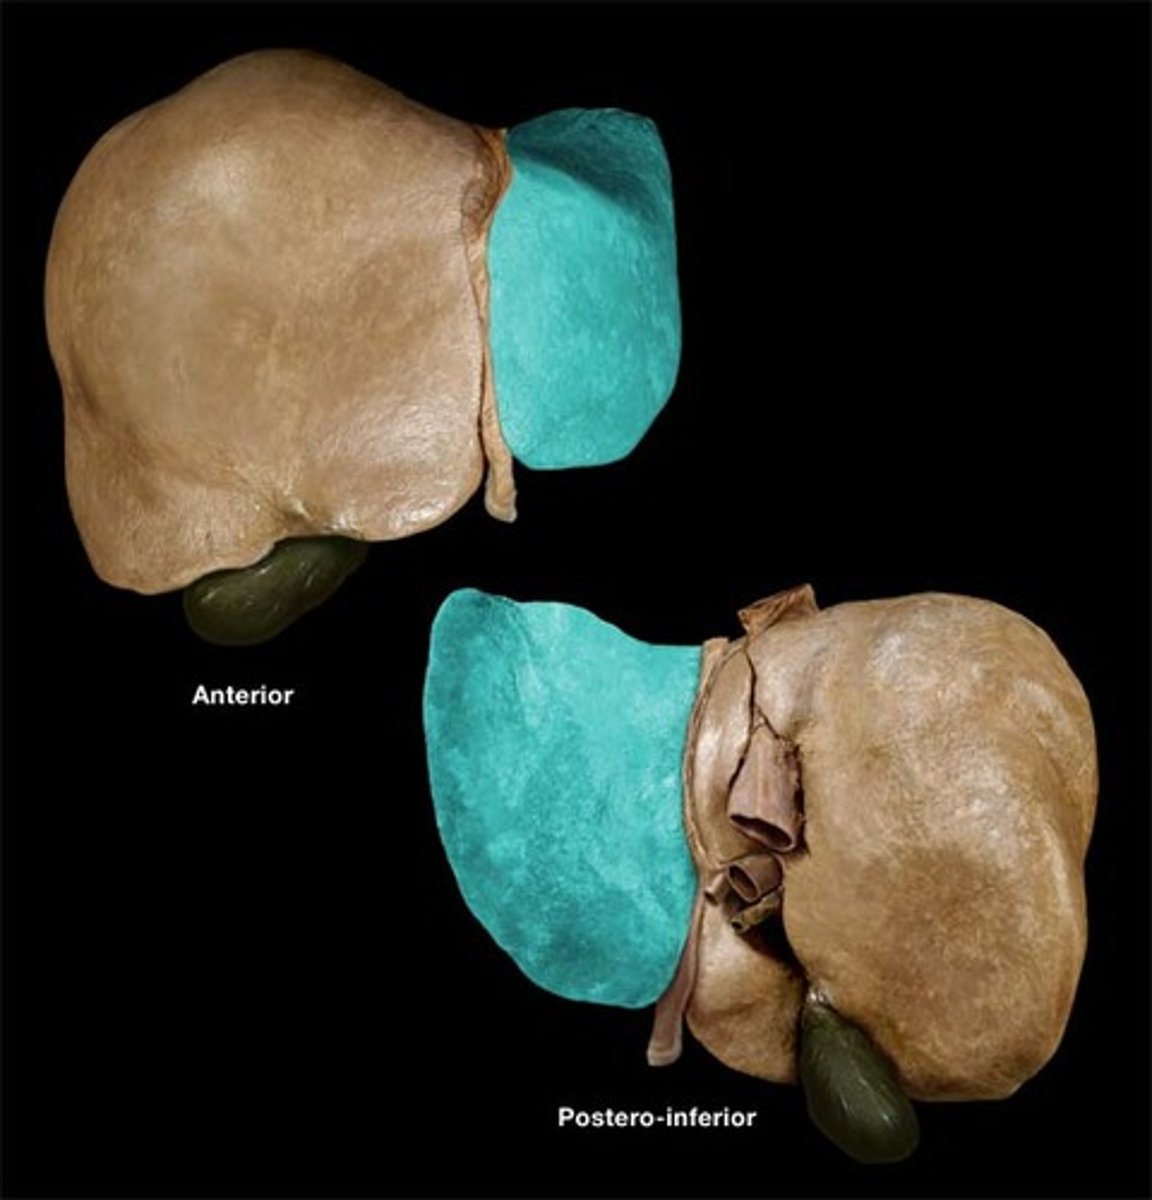

diaphragmatic surface (of liver)

bare area (of liver)

not covered by peritoneum